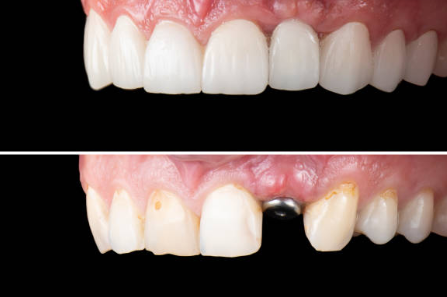

1. 외모

임플란트의 가장 큰 장점은 자연치아와 같은 외양 및 느낌 등 당당히 미소를 짓게 해주는 등 외모에 자신감을 가지게 해 줍니다.

4. 올세라믹

장점 : 자연치아와 가장 유사한 색을 가지고 있어 심미적으로 매우 우수합니다.